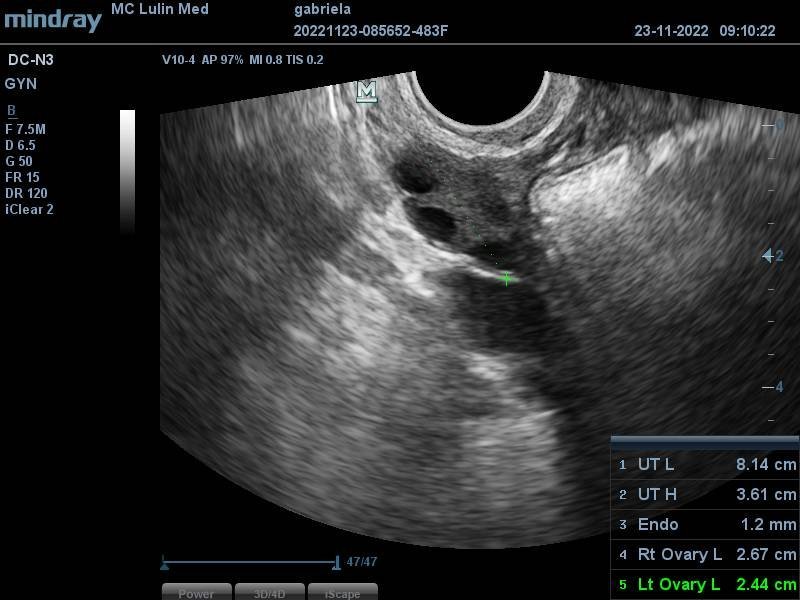

Какво представлява изображението от ехографията на 5-седмична и 2-дневна бременност?

Какво представлява жълтото тяло на ехографската снимка?

Какво представляват черните точки в матката на ехографската снимка?